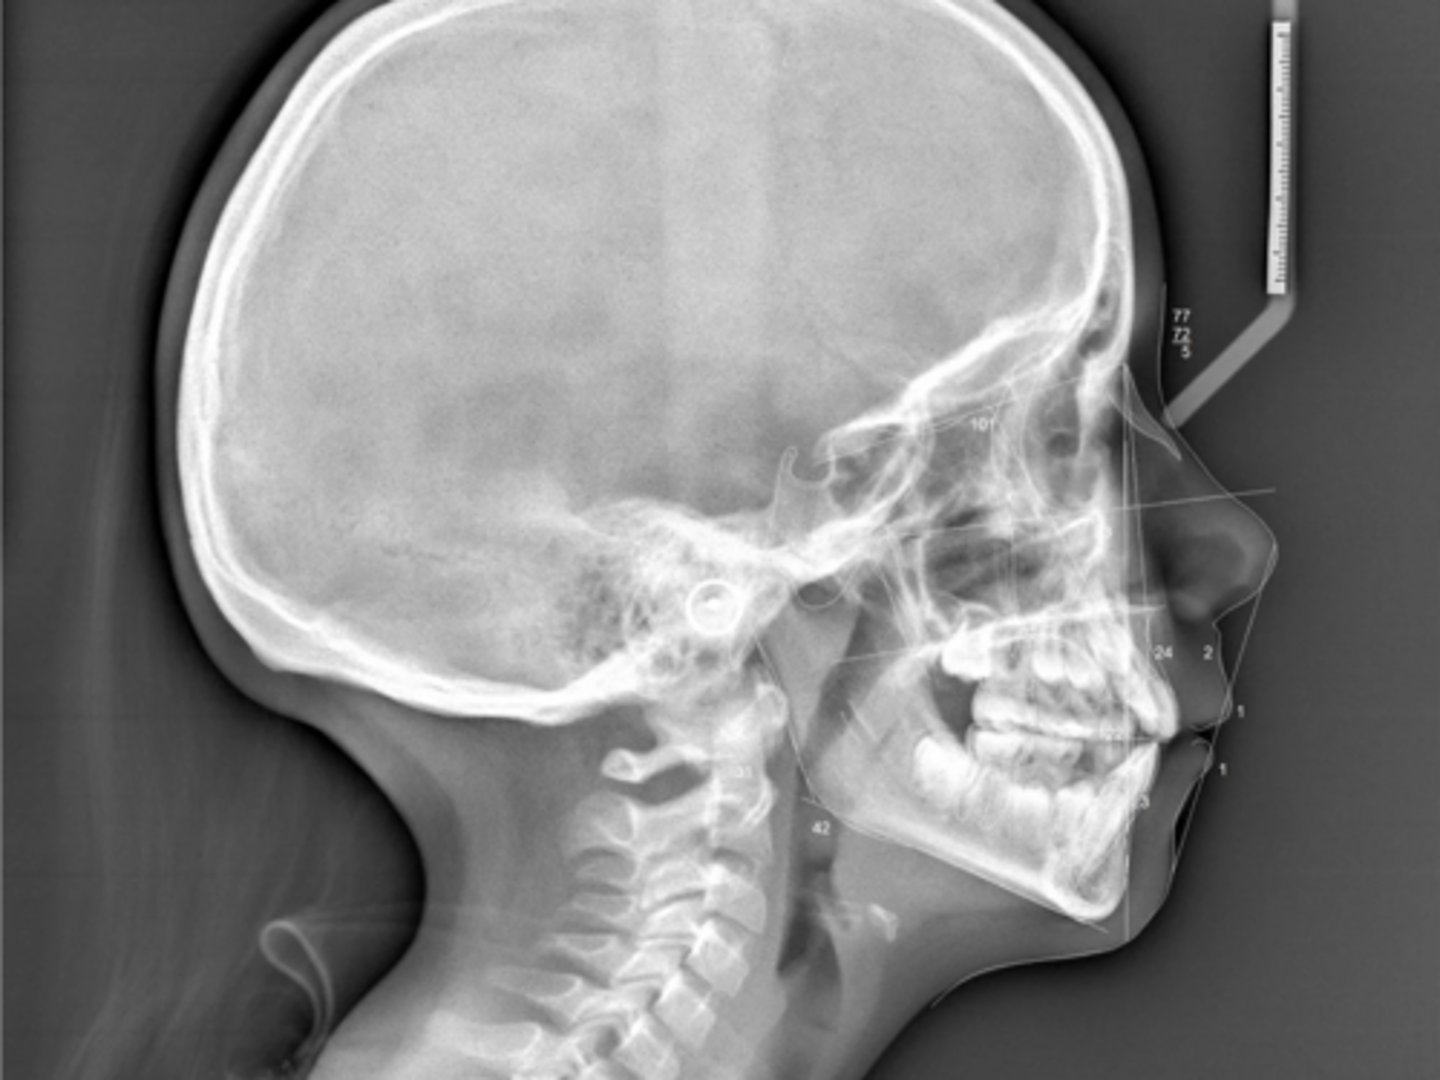

Class II

What type of skeletal malocclusion is this patient?

Hypodivergent

Are the hyper-, hypo-, o normo- divergent?

No

Are the maxillary incisors proclined/flared?